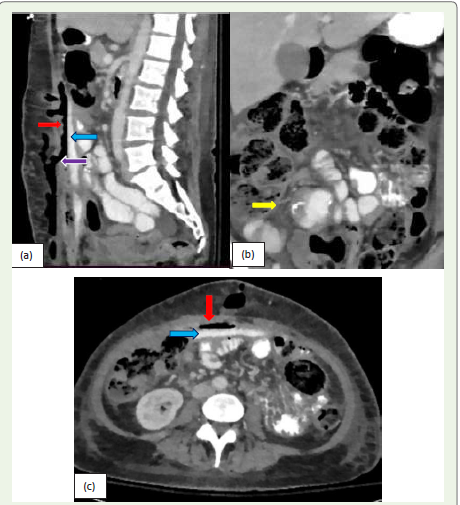

Figure 7: (a, b, c):Sagittal, coronal, and Axial CT images of a 53-yearold

female presenting with signs of sepsis. CT scan of the abdomen and

pelvis with oral and IV contrast demonstrates a large extra luminal complex

fluid collection (blue arrow), large air loculi (red arrow) and mesenteric

fat stranding (yellow arrow) in the anterior aspect of the abdomen, consistent

with the anastomotic leak. There is fistulous communication of extra-vasated

contrast (purple arrow) with the abdominal wall wound.